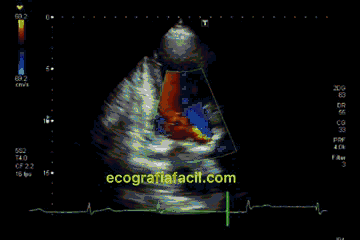

Aquí también pondremos el color para ver esa insuficiencia (clip 15). Y en este plano también pueden verse insuficiencias aórticas con jets excéntricos. Si ese es el caso, realizaremos las mismas maniobras que hicimos en el 5 cámaras.

Here we will also put the color to see that insufficiency (clip 15). And in this plane you can also see aortic insufficiencies with eccentric jets. If that is the case, we will perform the same maneuvers that we did in the 5 chambers view.